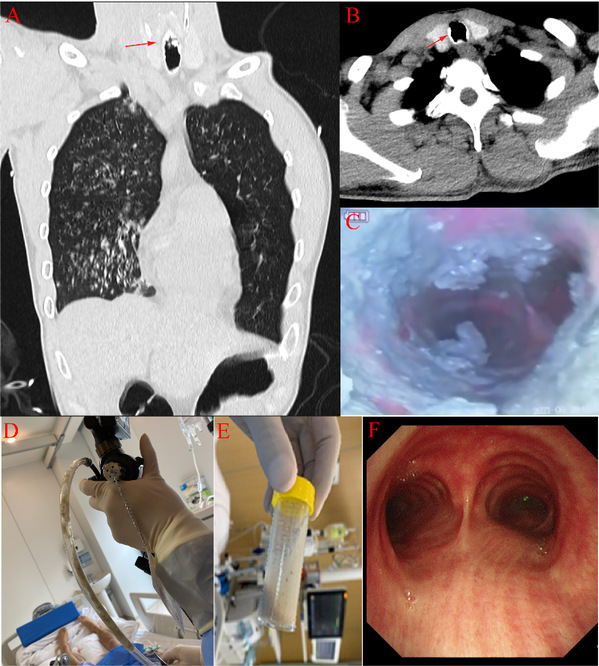

Aspirated cement is a rare and serious safety incident that can have severe consequences. Cement aspiration can lead to the solidification o...